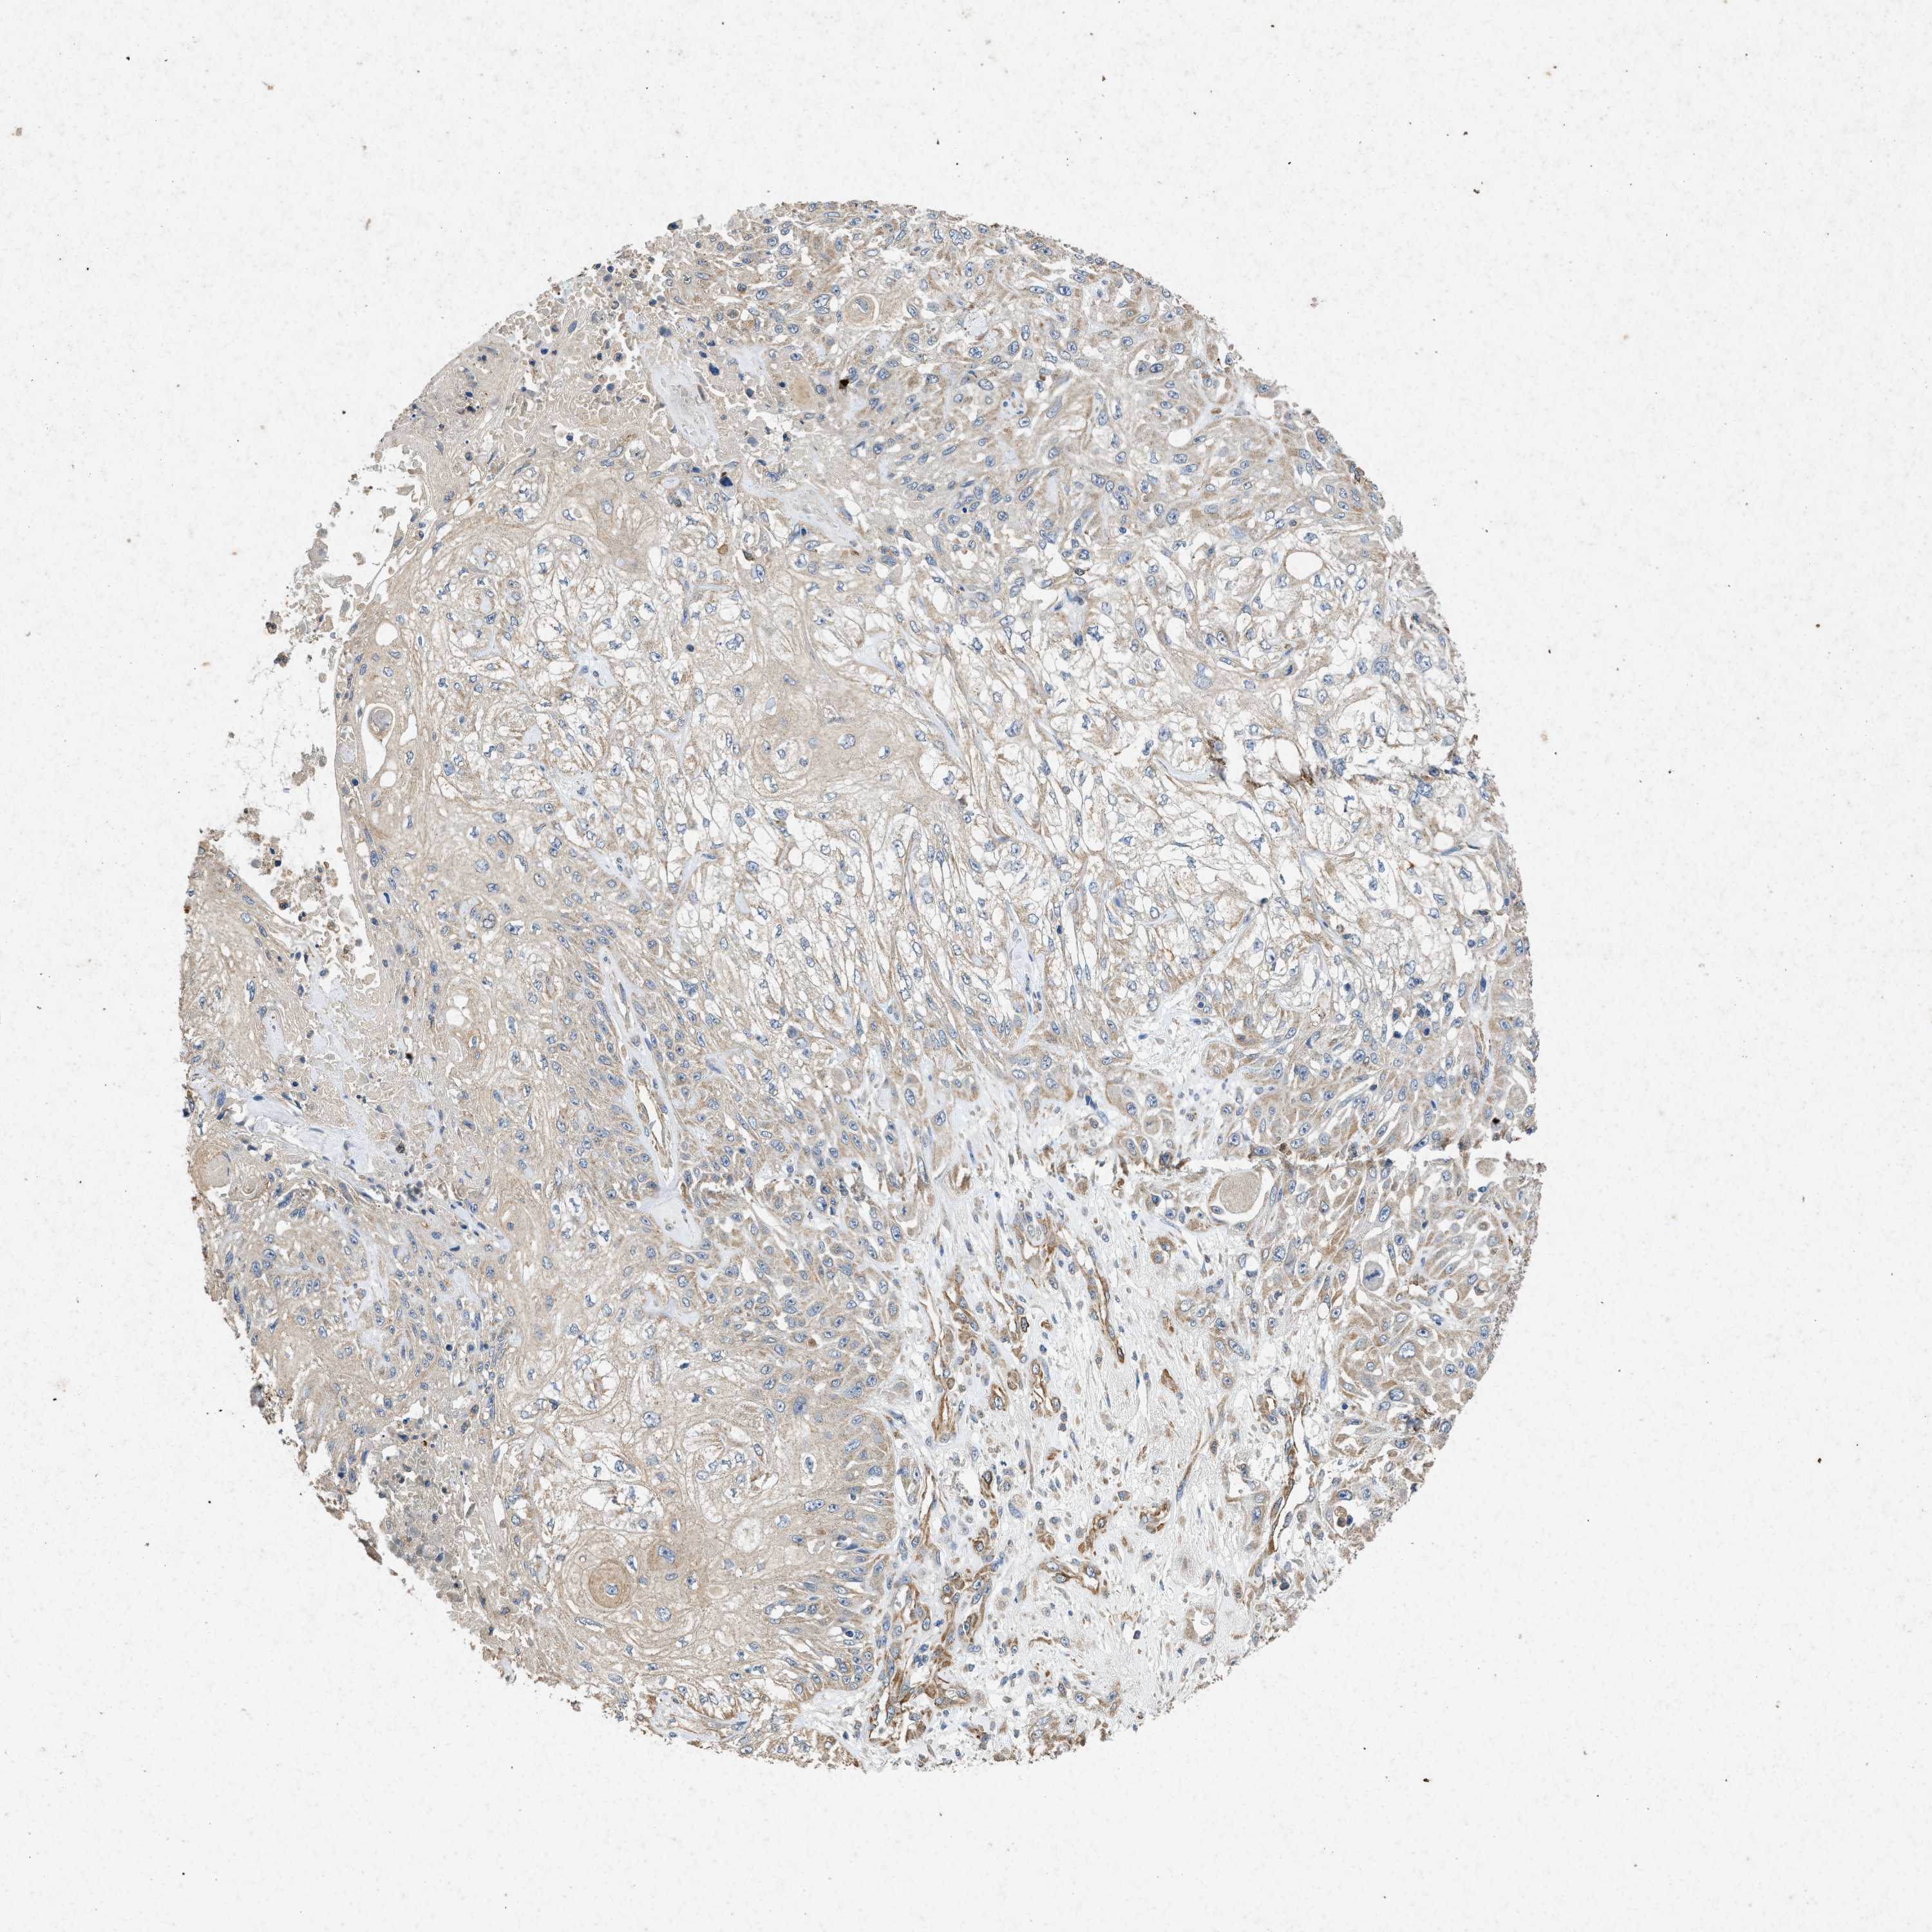

SKIN CANCER - Protein expressioni

A mouse-over function shows sample information and annotation data. Click on an image to view it in a full screen mode. Samples can be filtered based on level of antibody staining by selecting one or several of the following categories: high, medium, low and not detected. The assay and annotation is described here.

Note that samples used for immunohistochemistry by the Human Protein Atlas do not correspond to samples in the TCGA dataset.

Antibody stainingi

Antibody staining in the annotated cell types in the current human tissue is reported as not detected, low, medium, or high, based on conventional immunohistochemistry profiling in selected tissues. This score is based on the combination of the staining intensity and fraction of stained cells.

Each image is clickable and will lead to virtual microscopy that enables deeper exploration of all samples and also displays staining intensity scores, fraction scores and subcellular localization as well as patient and tissue information for each sample.

Antibody HPA015786

Staining

High

Medium

Low

Not detected

Intensity

Strong

Moderate

Weak

Negative

Quantity

>75%

75%-25%

<25%

None

Location

Nuclear

Cytoplasmic/membranous

Cytoplasmic/membranous,nuclear

Squamous cell carcinoma in situ, NOS